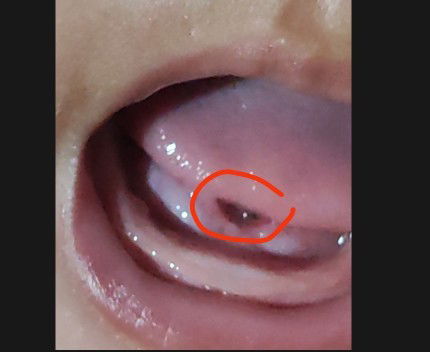

LIDAH BAYI

Hallo bun bawah lidah bayi saya kok seperti ini? Apakah ada yang sama?#seriusnanya #bantusharing

Saya baru ngeuh bawah lidah bayi seperti ini, ini normal atau tidak ya? Tapi tidak mengurangi volume menyusui dan tidak terlihat kesakitan juga